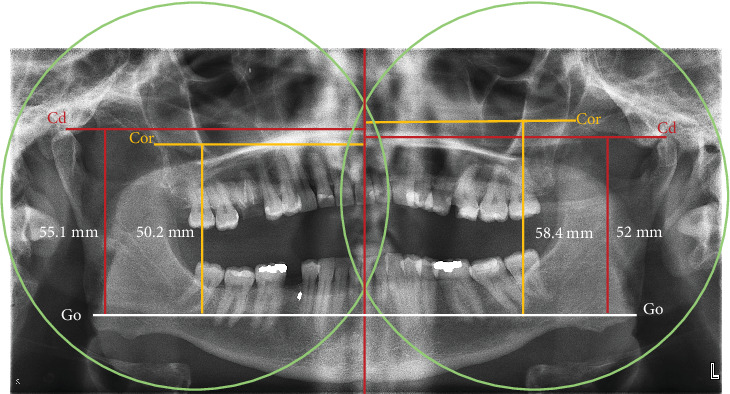

冠突的大小变化,由于增生或发育不全,可能会干扰正常的张嘴范围。摘要冠状突增生症是一种罕见的口腔颌面疾病,由于下颌冠状突的异常延长与颧弓的撞击,导致开口逐渐受限。这种情况提出了临床挑战,由于其非特异性性质的投诉,目前在患者。它的特点是逐渐无痛地限制张嘴。目前,确切的病因仍然没有定论;然而,遗传、激素、炎症或创伤的影响也有报道。在本文中,作者提出了两个病例报告的成年人怀疑单侧创伤后冠状增生和发育性髁发育不全,有历史的物理创伤造成的青春期。提供了一份简明的文献更新,以强调病因,准确诊断的意义,以及在恢复功能和美学方面实现有利结果的量身定制的治疗方式。

Changes in the size of the coronoid process, due to hyperplasia or hypoplasia, may interfere with the normal range of mouth opening. Coronoid hyperplasia is a rare oral and maxillofacial disease which might result in progressive limitation of mouth opening due to the impingement of an abnormal elongated mandibular coronoid process on the zygomatic arch. This condition presents with clinical challenges due to its nonspecific nature of complaints that present in patients. It is characterized by gradual painless restriction of mouth opening. Currently, the exact etiopathology still remains inconclusive; however, genetic, hormonal, inflammatory, or traumatic influences have been reported. In this paper, the authors present two case reports of adults with suspected unilateral posttraumatic coronoid hyperplasia and developmental condylar hypoplasia that have a history of physical trauma inflicted during adolescence. Provided is a succinct update of literature to highlight the etiopathogenesis, significance of accurate diagnosis, and tailored treatment modalities in achieving favorable outcomes to restore function and esthetics.